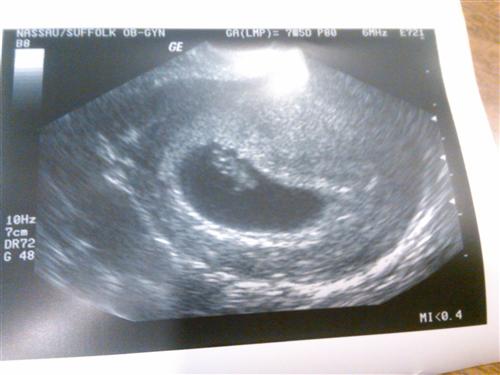

7.5 wks